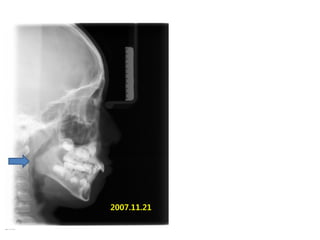

S.H. Jang

1999.10.14/M

C.C

• Max. protrusion

• Lower crowding

Dx

• Mouth breathing, retro-positioned tongue

Goal

• Lip seal(Adenoidectomy and Tonsilectomy)

• Establish tongue posture with T4K

2006.07.21

A &T 2008.01 Tr start

2007.11.21